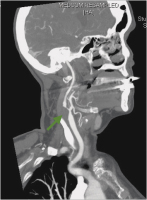

MR-Angiographie

Abbildung 1: Präoperative MR-Angiographie: Verschluss des Truncus brachiocephalicus (grüner Pfeil) und der linken Art. carotis communis und interna, hochgradige Abgangsstenose der linken Art. vertebralis (grüner Pfeil).